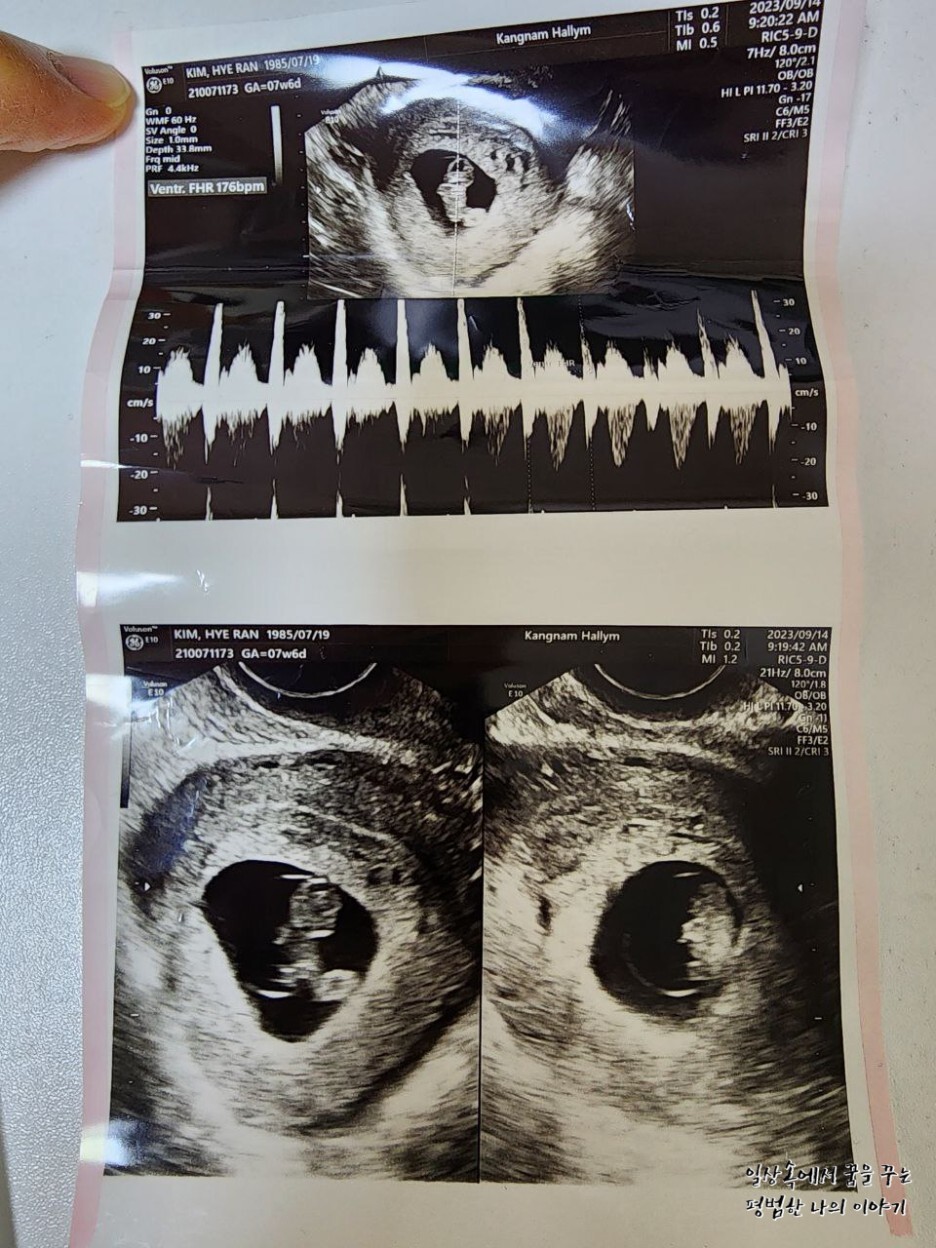

일주일 만에 다시 만난 레오나는 그 새 무럭무럭 자라 있었는데 너무나 귀여운 젤리 곰 모양을 하고 있었다.(초음파를 통해 젤리 곰 형태의 귀여운 태아를 볼 수 있는 주차 수는 보통 8~9주이므로 일부러 이때를 맞춰 산부인과에 방문하는 산모도 있다) 얼굴, 손 그리고 발의 형태를 모두 볼 수 있었는데 둘째인데도 여전히 내 뱃속에서 생명체가 자라고 있다는 사실은 늘 신기하다. 그리고 매번 산부인과에 방문해 성장해 있는 모습을 볼 때마다 감탄한다. 아무래도 첫째 육아를 하면서 임신 과정을 겪는 거라 첫째 임신 때보다 덜 조심하게 되고 덜 신경 쓰게 되고 산부인과도 덜 가게 돼서 항상 미안한 마음이 든다.